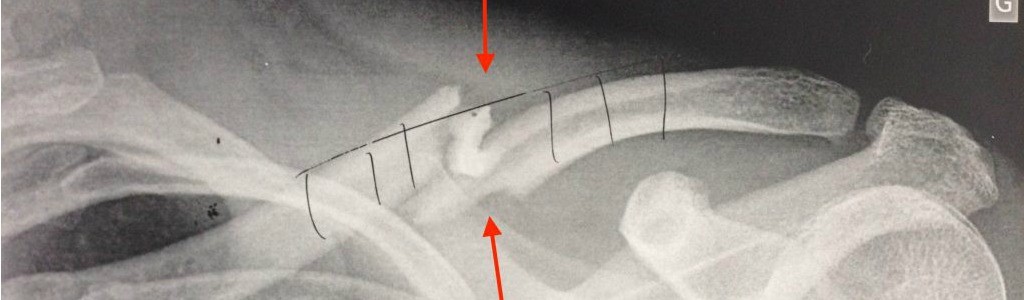

Après des tests sur des lapins et des moutons qui ont donné d’excellents résultats, le traitement Osteogrow a été suivi avec succès par dix patients à l’Hôpital des Sœurs de la Charité à Zagreb pour des formes sévères de fracture du radius et des fractures du tibia non consolidées à répétition. Aucune complication, ni effet secondaire n’ont été enregistré. À Vienne, des chirurgiens utilisent la nouvelle thérapie pour traiter des patients atteints de pathologies dégénératives de la colonne vertébrale. Les essais cliniques se poursuivent et au total, 75 patients auront suivi ce nouveau traitement.